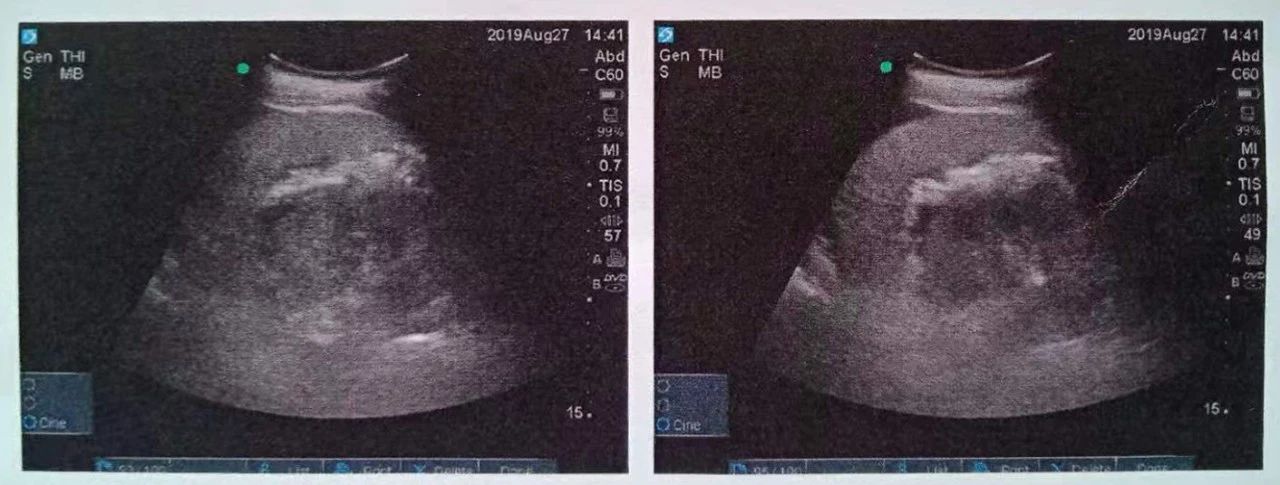

術(shù)中,北京愛(ài)康醫(yī)療集團(tuán)泌尿集團(tuán)首席專(zhuān)家郭駿博士精心設(shè)計(jì)手術(shù)通道,只在患者體表鉆出兩個(gè)0.5厘米的小洞,由于曾奶奶右側(cè)上位腎位置高,靠近肝臟和肺下葉,容易出現(xiàn)肝臟和肺的損傷,遂在B超的引導(dǎo)下精確穿刺腎結(jié)石的最高點(diǎn),逐級(jí)擴(kuò)張后建立皮腎通道。這時(shí)屢次“惹禍”的腎結(jié)石清楚的顯露在手術(shù)屏幕上,結(jié)石呈淺黃色,表面覆蓋淺褐色的膿苔,然后使用鈥激光將結(jié)石擊碎后取出。歷時(shí)一個(gè)半小時(shí),結(jié)石全部清除,手術(shù)結(jié)束。

這種方式是在超聲實(shí)時(shí)引導(dǎo)下,在腰部經(jīng)皮膚穿刺建立通道(俗稱(chēng)打洞)進(jìn)入腎臟,找到腎結(jié)石后用鈥激光碎石。